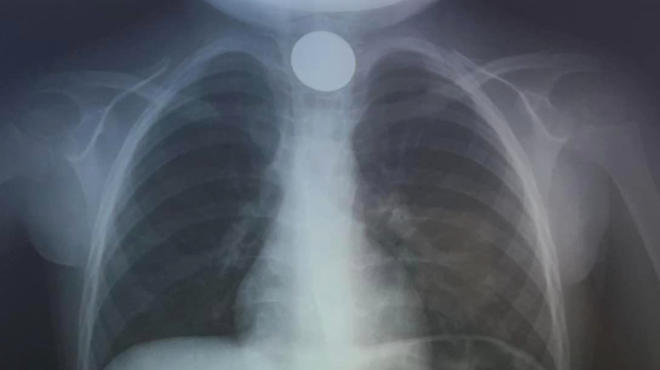

Κατά την άφιξη στο ΠΑΓΝΗ, οι γιατροί προχώρησαν αμέσως σε ακτινογραφία για να εντοπίσουν τη θέση του νομίσματος και στη συνέχεια προχώρησαν στην επείγουσα αφαίρεσή του. Με γρήγορη επέμβαση, οι γιατροί αντιμετώπισαν επιτυχώς την κατάσταση, επιλύοντας γρήγορα το πρόβλημα.